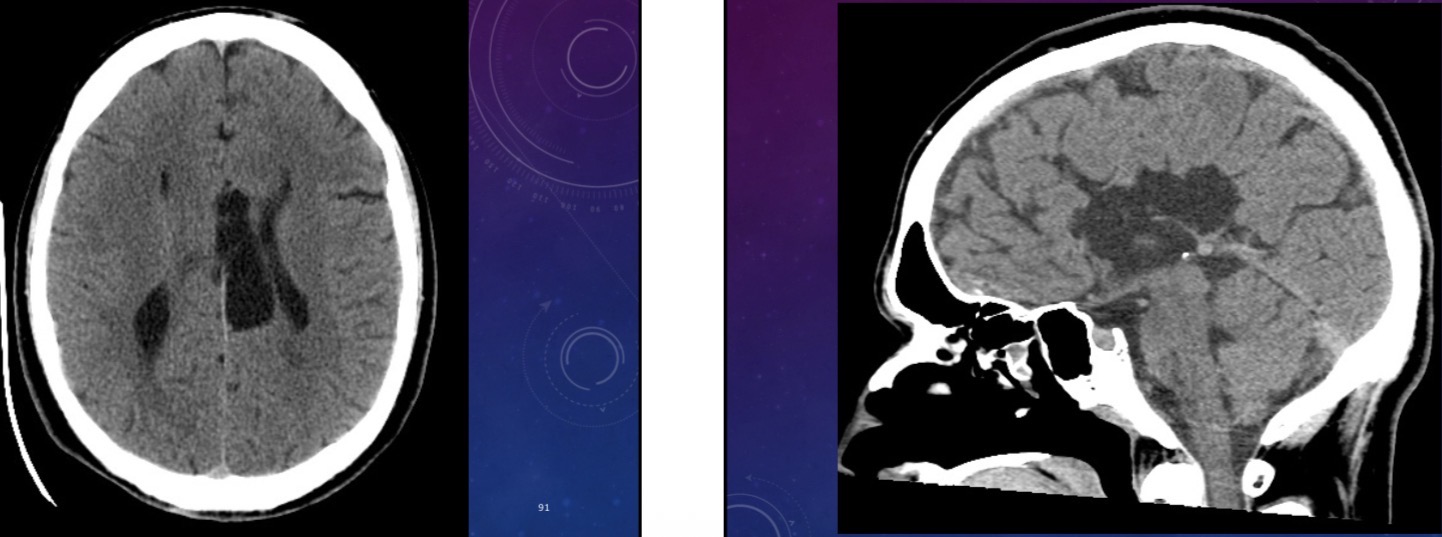

10-year-old male has a history of intermittent headaches for the past five months.

Pineoblastoma

Pineal gland tumor with mets to the frontal lobe